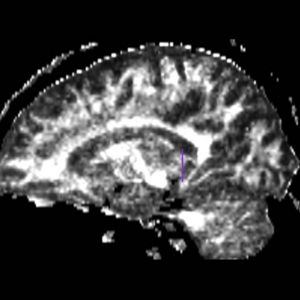

The ROI1 was drawn on the sagittal slice, 5 slices superior to the anterior commisure (Fig. 8 & 10). The ROI2 was drawn on a coronal slice where the crux of the fornix was present. It was not always the same slice for both sides (Fig. 9 & 11).

Figure 9. Coronal View of ROI 2 (left=11, right=13)

Figure 11. Sagittal View of Fornix, ROI 2 (right)

The color coding of the resulting ROIs is as follows:

ROI 1: Left & Right (16)

ROI 2: Left(5) - Right(15)